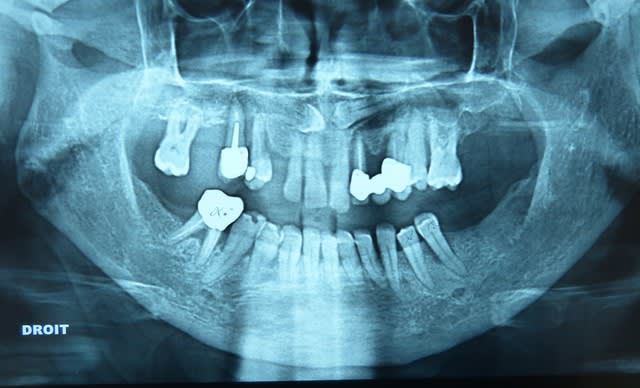

Voici le cas, patient d'une cinquantaine d'année se présentant pour solution prothétique.

Il a déjà un stellite mandibulaire de 10 ans, mais les édentements au maxillaire sup n'ont jamais été compensé.

Resultat: egression +++ de la 27 et 25

Tiens là, au maxillaire l'indication était un complet, mais la patiente pas prête, et surtout pas envie de se faire retirer 13 et 23, alors j'ai conservé 17 endo+reconst directe, 12,11,21,25,26+ 23 et 13 incluses.

Pap résine, et hop! Là c'est les Xgames de l'adjointe, à ne pas copier!